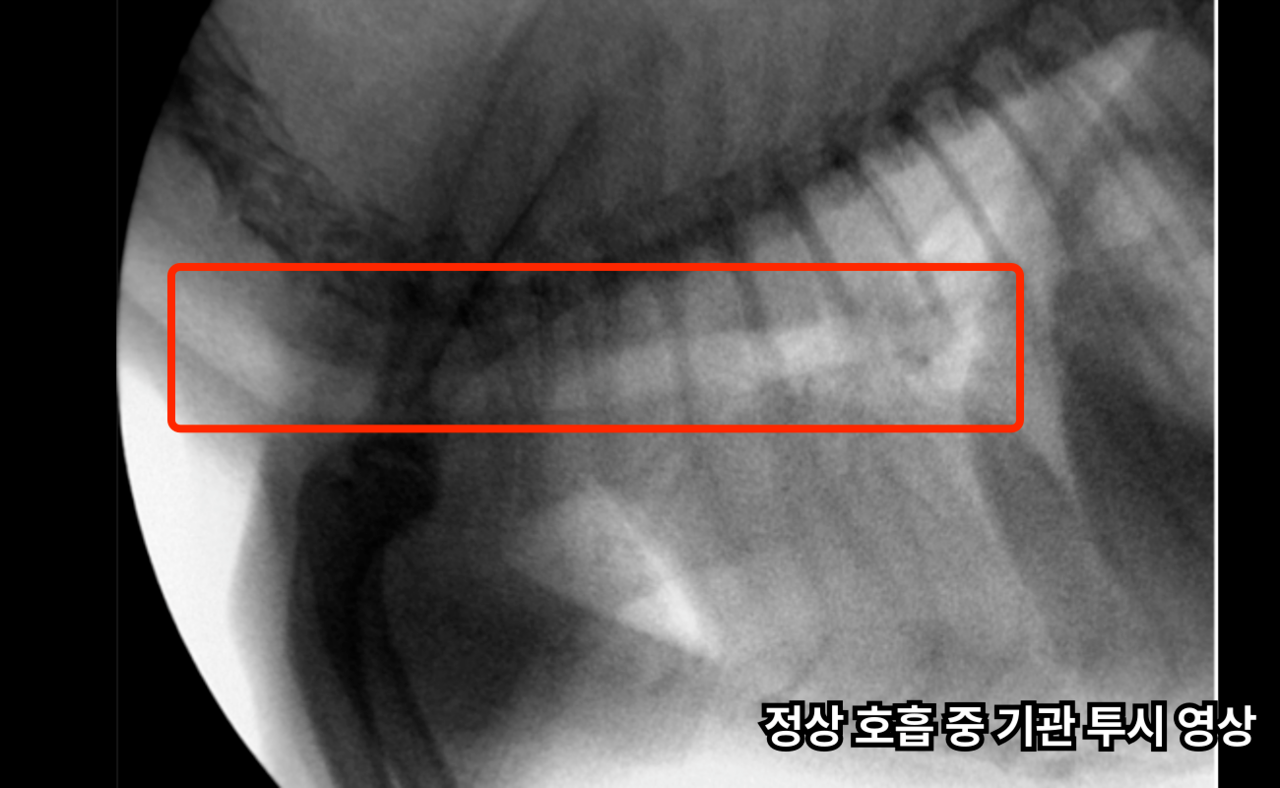

비전플로우는 실시간 투시 영상을 통해 숨쉴 때의 기관의 구조와 변화를 평가합니다.

Fluoroscopic examination of the trachea

기관 구조를 실시간 확인하는 비전 플로우 검사

비전플로우 검사를 통해 실시간 촬영을 진행하여

숨을 들이마실 때, 내쉴 때 기관이

눌리거나 좁아지는 지 실시간으로 확인합니다.